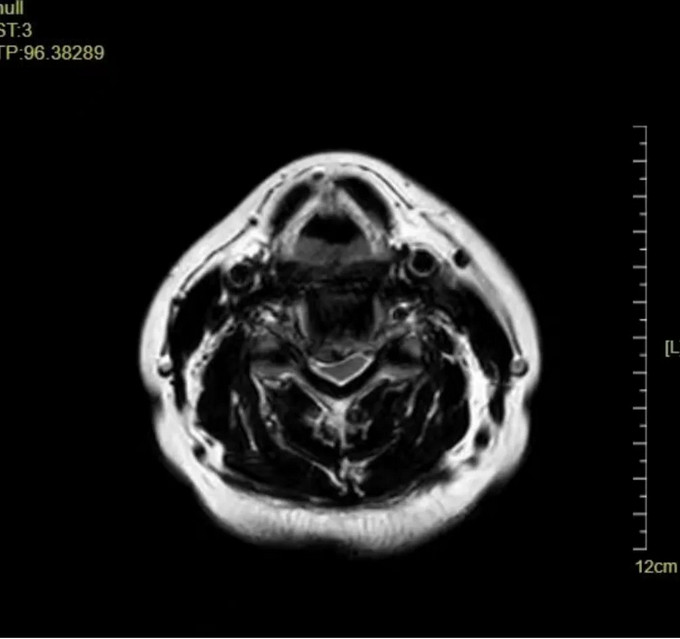

頸椎MRI橫斷位

頸椎MRI矢狀位,可以看到患者的頸神經(jīng)被明顯壓迫

頸椎MRI矢狀位 頸神經(jīng)壓迫程度明顯減輕